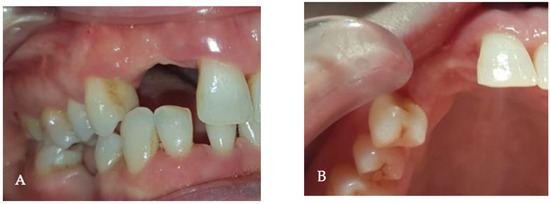

Background and Objectives: Alveolar ridge augmentation in the complex bone defect is a popular topic in implantology. Guided bone regeneration (GBR) is one of the most commonly applied methods to reconstruct alveolar bone. The application of a membrane is the fundamental principle of GBR. There are many membrane types used in oral surgery, but the advantage of the titanium mesh is the rigidity which provides space maintenance and prevents contour collapse. The smooth surface also reduces bacterial contamination. Using computer-aided design (CAD) and computer-aided manufacturing (CAM) in dentistry allows us to obtain the perfect architecture form of the mesh, which covers and protects the bone reconstruction. Case presentation: We present a surgical case of a 27-year-old female patient with severe aesthetic bone atrophy after a deficient odontectomy. Based on the GBR clinical applications, the technique consists of bone reconstruction and a customized titanium mesh application. Using mesh titanium in this case presentation was a reliable alternative to perform a lateral alveolar bone augmentation and reconstruct ridge deformities before reaching an ideal implant placement. Conclusions: According to our case report, the customized titanium mesh could be a valuable option for guided bone regeneration in aesthetic maxillary defects. Full article